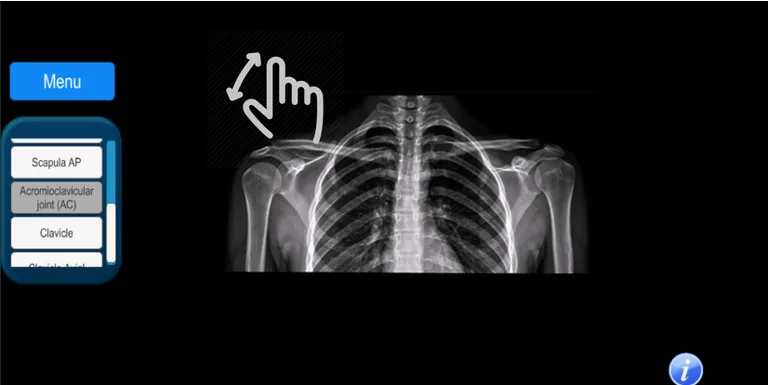

It is an app that allows the user to know the radiological projections that are used daily in a patient care. It covers all areas of the human body with more than 100 digital radiographs: skull, maxillofacial, spine, chest, abdomen, pelvis, upper and lower extremities.

The anatomy of the studied area is described, as well as the technique used for positioning the radiographic projection.

It allows the user to zoom in or out of the radiographic image.